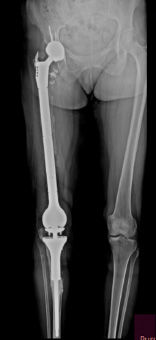

Klasik osteosarkomun cerrahi tedavisi, tümör ve tümör dokusu ile temas etmiş tüm bölgelerin, üzerinde yeterli kalınlıkta sağlıklı doku örtüsü bırakılarak, tümöre dokunulmadan çıkartılmasıdır. Kemoterapi, tümörü küçülterek çıkartılmasını kolaylaştırmak, bölgesel tekrar (lokal nüks) riskini azaltmak ve sistemik yayılmayı (metastaz) engellemek için ameliyat öncesi (neodjuvan) ve ameliyat sonrası (adjuvan) mutlaka uygulanmalıdır. Neoadjuvan kemoterapi ile mikrometastazların önüne geçmeye çalışılır.

Akciğerlerde ortaya çıkabilecek metastazlar kemoterapi ve cerrahi ile tedavi edilirler. Hastalığın tamamen tedavi edilebilme oranı doğru ve başarılı yöntemlerle % 65-70 olarak belirlenmiştir.